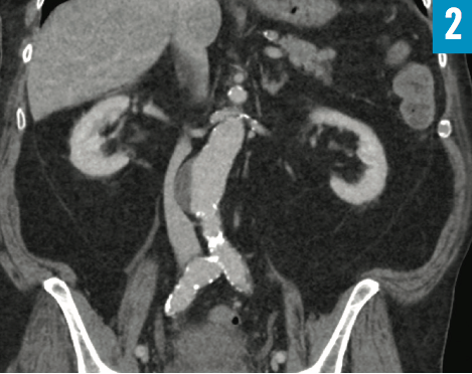

A 90-year-old man presented to the emergency department with 1-day history of tachypnea, dyspnea, and lower abdominal pain. His multiple comorbidities included coronary artery disease, obstructive sleep apnea, hypertension, hyperlipidemia, gout, transient ischemic attack, and benign prostatic hyperplasia with placement of a long-term indwelling urinary catheter for years.

His vital signs included a blood pressure of 156/79 mm Hg, a heart rate of 92 beats/min, a respiratory rate of 36 breaths/min, a temperature of 36.0°C, and oxygen saturation of 96% on room air. Abdominal examination revealed suprapubic tenderness without rebound tenderness or guarding. Urinalysis results were suggestive of urinary tract infection. Computed tomography scans of the abdomen/pelvis were obtained (Figures 1 and 2).